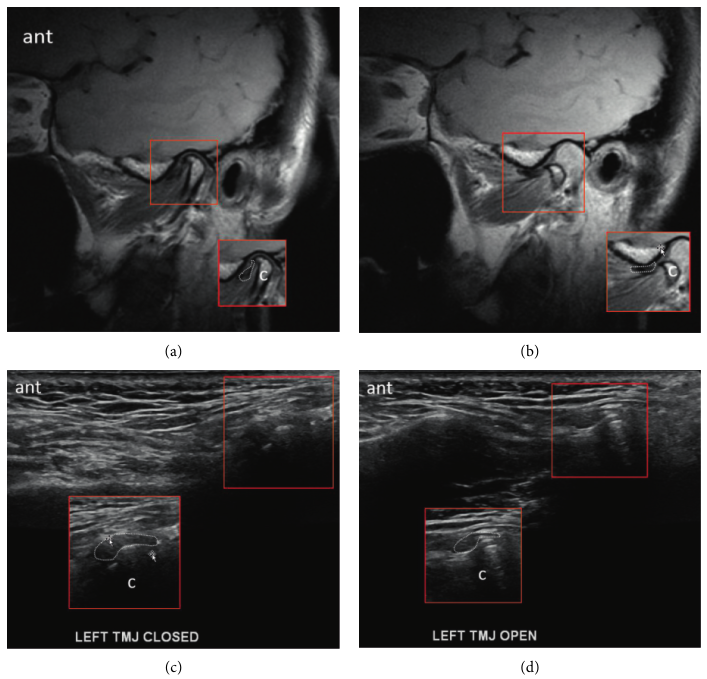

Friedman의 연구에 따르면,

'고해상도 하키스틱 프로브 초음파'로

턱관절 디스크의 위치와 움직임을

정밀하게 볼 수 있습니다.

과거에는 비싼 MRI를

찍어야만 알 수 있었던

디스크의 마모, 염증

퇴행성 변화로 뼈가 자라나는 골극 등을

'정밀 초음파'로

확인할 수 있게 된 것이죠.

초음파로 1차적으로 확인한 후에

병변이 의심된다면

3.0T MRI 검사를 찍어야죠.